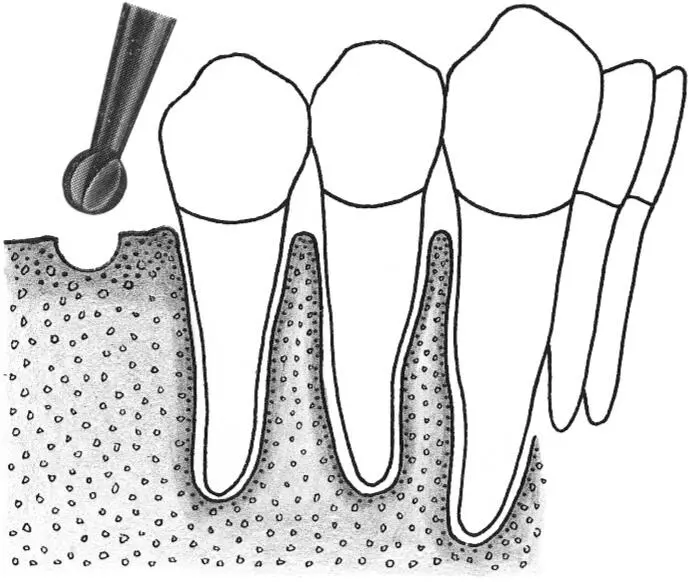

Fig 1-3Correction of the position and axis of the implant site preparation.

Fig 1-3a The preparation of the implant site begins with the use of the nos. 1 and 2 round burs to mark the position of the implant site.

Figs 1-3b and 1-3c Any required changes to the marking made with the first round bur can be accomplished with the no. 2 round bur, as shown in this occlusal view. These initial steps for the preparation of the implant site ensure the correct implant position orofacially and mesiodistally.

Fig 1-3d After the use of the first pilot drill (A) , a 2.2-mm-diameter guide pin is used to check the axis and depth of the implant preparation (B) . Any incorrect axis orientation can be adjusted with the same 2.2-mm-diameter pilot drill (C and D) and then followed with the 2.8-mm-diameter spiral drill (E) .